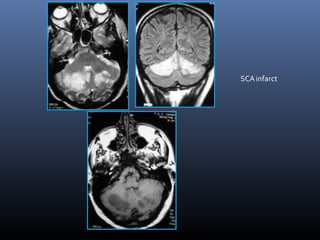

SCAinfarct